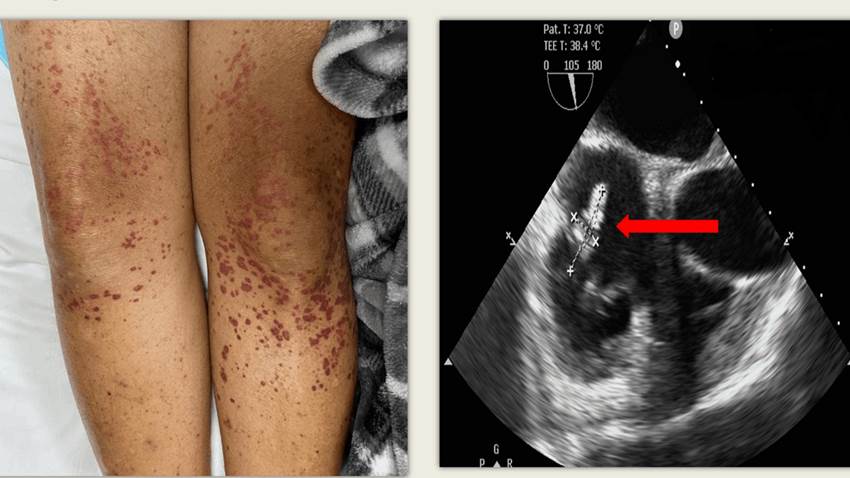

Endocarditis de la válvula tricúspide provoca extraño tipo de vasculitis leucocitoclásticas en paciente

La endocarditis continúa demostrándole a la medicina que su poder va más allá de lo contenido en literatura. Y es que en entrevista con la Revista Med...